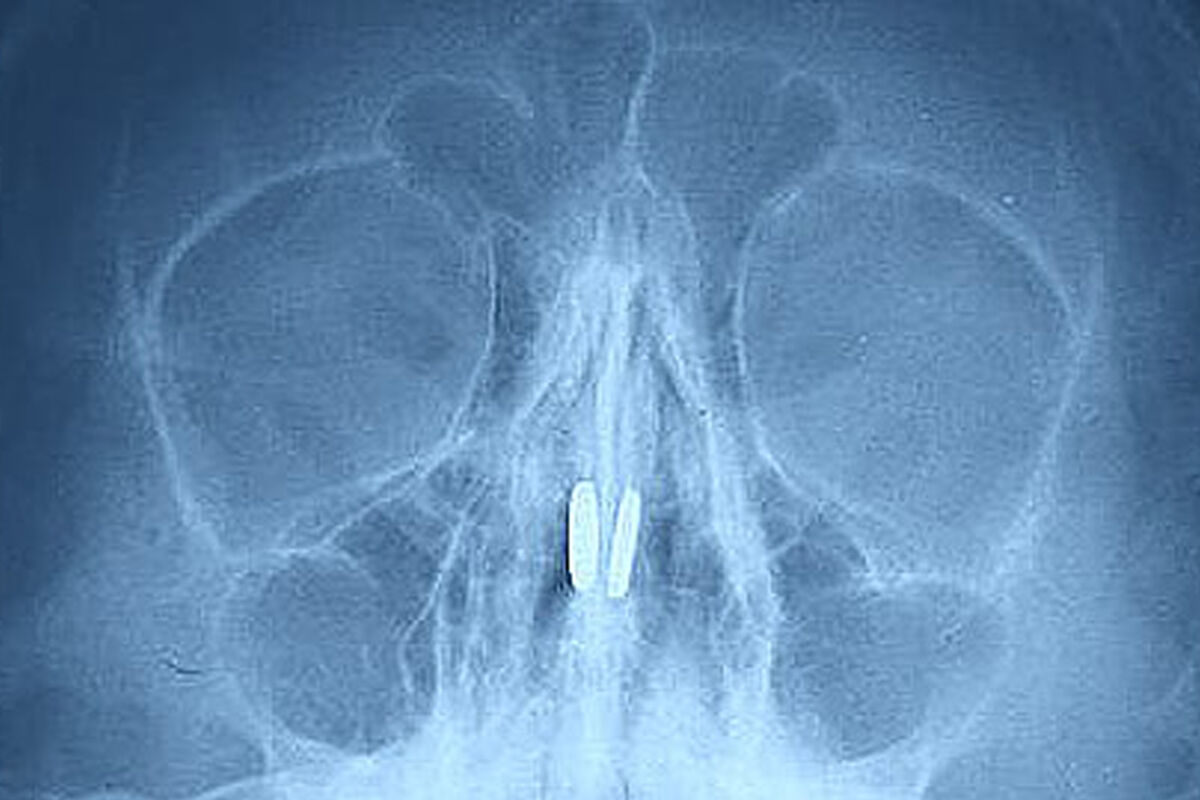

Маленький пациент был доставлен в медицинское учреждение с жалобами на боль в носу и проблемы с дыханием. В ходе обследования в носовых пазухах были обнаружены магниты от игрушки, которые притянулись друг к другу через носовую перегородку.